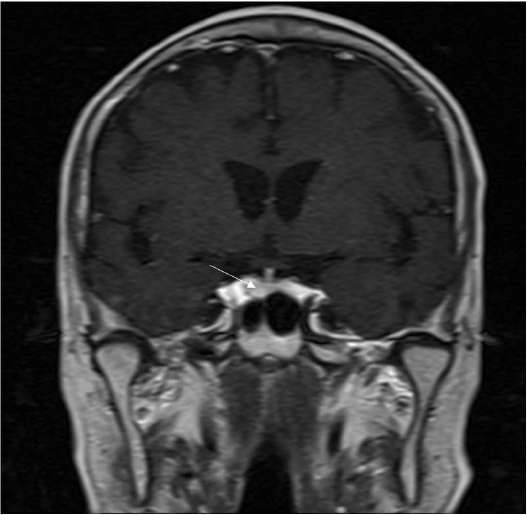

Figure 1.

Coronal T1-weighted image shows a pituitary gland that was not enlarged. Coronal T1-weighted image obtained after intravenous bolus injection of contrast material led us to suspect a 7 mm mass with decreased enhancement of the pituitary gland (white arrow).